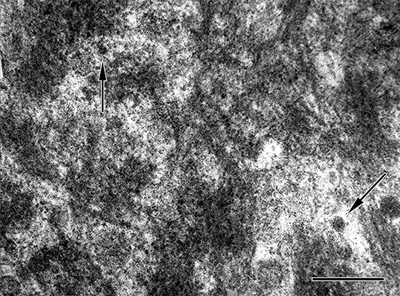

Viewed in the electron microscope, Aβ-amyloid fibrils in the plaque core are densely packed and often bundled to form a patchy matrix, and viable cellular processes there are largely absent. The more loosely organized Aβ-amyloid sheaves in the space and corona interdigitate with cellular elements such as glial processes and neurites (Figure 12; see also Figures 18 and 20). Embedded in the fibrillar meshwork of amyloid in plaques, various small, spherical particles can be seen (Figure 13). The origin and significance of this material is obscure, but it could account for some of the non-Aβ substances that have been detected in the cores of Aβ plaques (see Section 7). One possibility is that these vesicles originate from intracellular multivesicular bodies, which have been shown experimentally to be an important site of APP/Aβ biology [196-201]. In this regard, vesicular structures ranging from 50 to 300nm in diameter have been reported among the amyloid fibrils in a cell culture model of Aβ amyloid deposition [202].

Figure 12. Ultrastructure of fibrillar Aβ in the plaque corona (left) and core (right) in an AD patient. Bar = 500nm for both images.

Figure 13. High-magnification electron micrograph of a portion of the core of an Aβ-amyloid plaque in an AD patient. The fibrillarity of the material is less evident than in more peripheral zones. Unidentified particles (2 are marked by arrows) of various sizes and densities are interspersed among the amyloid fibrils; these can be found both in the core and corona. Bar = 200nm.